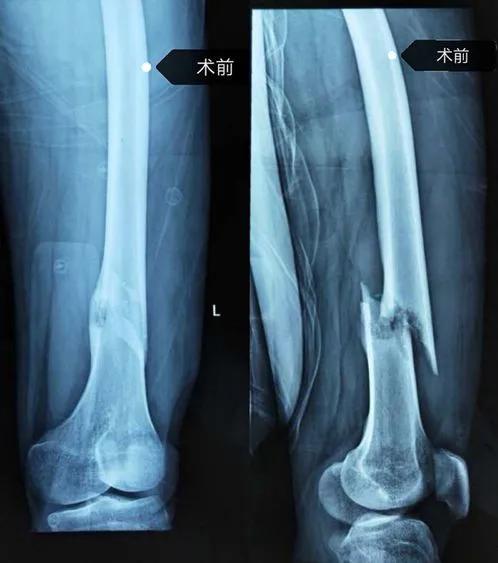

左股骨瘤段骨切除骨水泥占位器植入骨折外固定及术后图片

手术由创伤骨科主任王金山主刀,据王金山介绍,张先生的手术分两次进行。第一次术中把肿瘤切除后旷置,依据CT扫描结果定制3D打印假体,在四周以后进行假体置入术。手术最大难度是肿瘤段骨完整切除,关键技术是诱导膜技术和私人订制3D打印假体。3D打印假体放入后,诱导膜促进骨质再生及修复,手术才能成功。做好充足的手术预案后,在麻醉科的协助下,创伤骨科团队成功将肿瘤切除,并将3D打印个性化定制的钛合金假体完美置入。此例手术由创伤骨科自主完成,该术的成功开展,标志着创伤骨科在应用3D打印技术实施骨肿瘤的个性化治疗中取得了新突破。